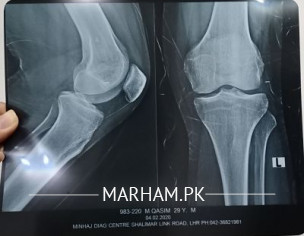

i was feeling a cracking sound in my left knee joint . can dr plz see my xray attached and tell me if anything looks wrong

No apparently abnormal

X-ray is apparently normal and cracking sound are cause by multiple reasons need to be examine.

X-ray k sth sth apky knee ka examination b zaruri Hy..

kisi achy Orthopedic Surgeon ko check krwa lijye..